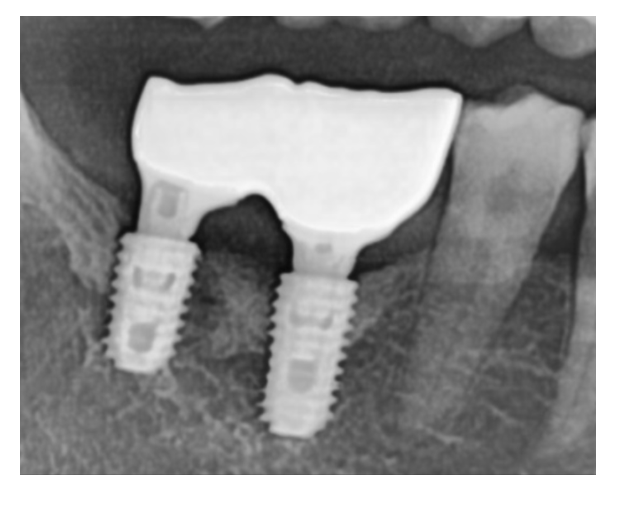

임플란트는 뼈에 고정된 인공치근(뿌리)과

그 위에 연결된 보철물(크라운)로 구성됩니다.

이때 크라운 주변 잇몸과 치아 사이에

아주 좁은 미세 틈새가 존재합니다.

여기에 음식물 찌꺼기나 세균이 쌓이면

자연치 못지않게 세균 번식이 일어나며 냄새가 날 수 있어요.

250308 보철물 경계 부위로 세균이 들어갈 수 있어요